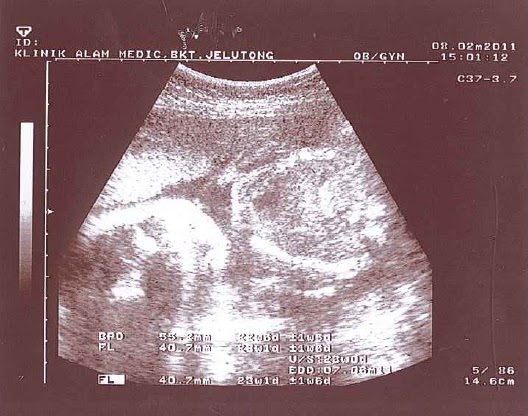

![]() |

| 1st peek into the belly; 3 months old |